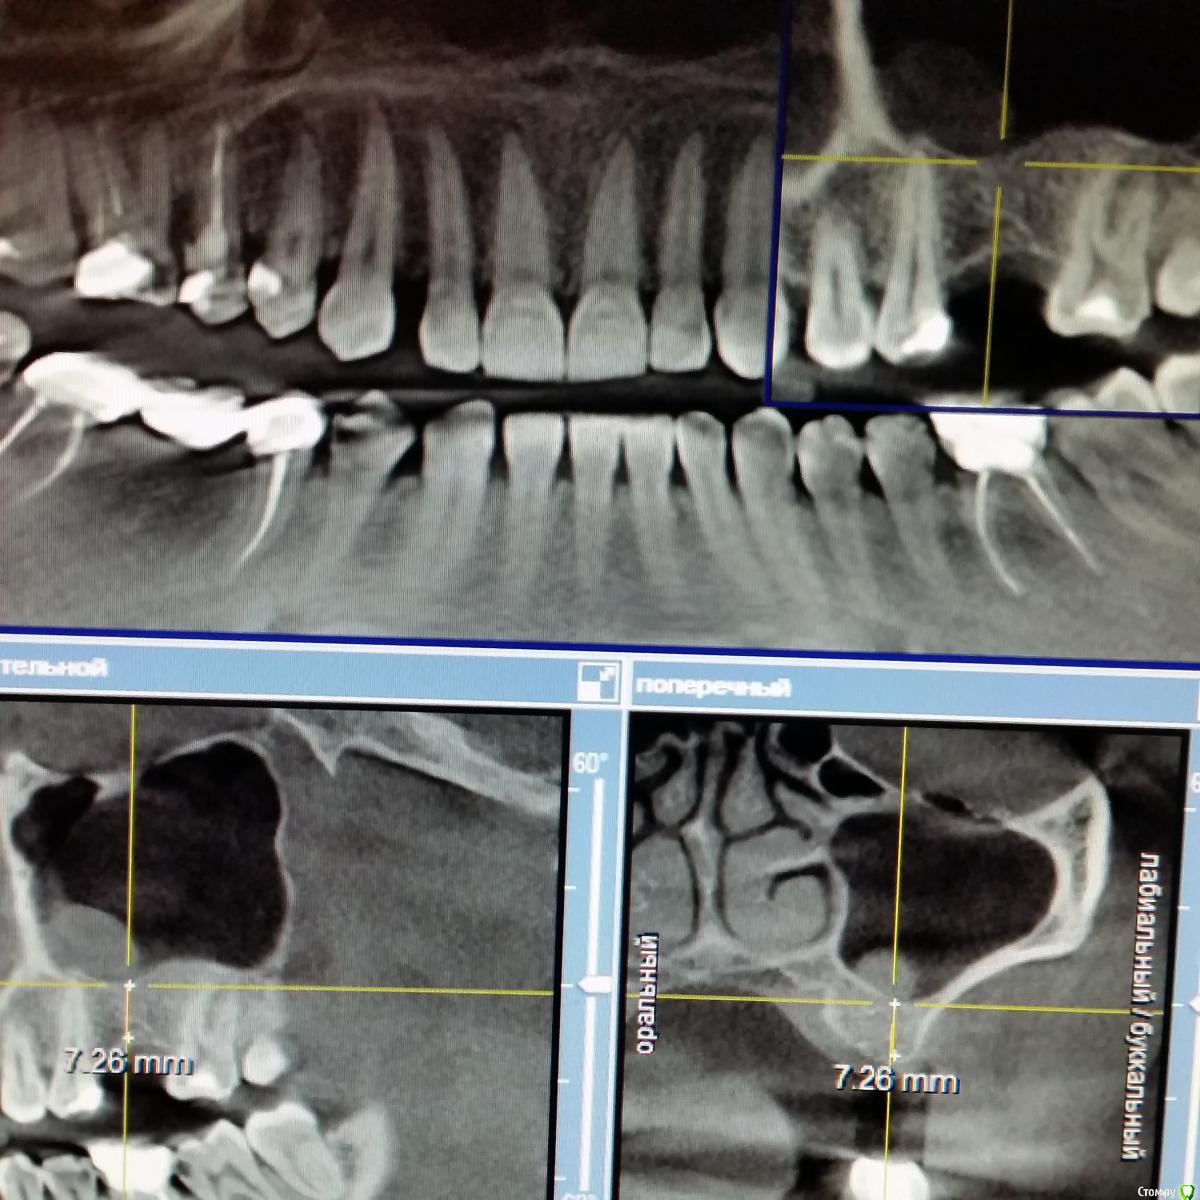

inycik Опубликовано 12 декабря, 2016 Поделиться Опубликовано 12 декабря, 2016 Уважаемые специалисты, помогите советом. Мнения врачей расходятся. Все зубы перелечила. это кт до лечения. Сейчас под временными коронками. Предлагают имплантацию 1.5,2.5 и 4.5 (убрать мост, т.к. 4.6 сильно разрушен). 1.5 удалить и сразу же имплантВопросы. 1. У меня грудной ребенок. Можно ли делать имплантацию2. Нужен ли синус-лифтинг3. Обнаружили проблему в пазухе, что это и может ли повлиять на имплантацию4. Может лучше подождать, чтобы зажило после удаления зубаСсылка на кт https://drive.google.com/file/d/0B7fYoL1llb1HQnEyM0FmOVFxVEU/view?usp=sharing Ссылка на комментарий

Nazim_NV86 Опубликовано 15 декабря, 2016 Поделиться Опубликовано 15 декабря, 2016 Вы выложили 2.5В такой ситуации можно установить 8-9мм имплантат с закрытым лифтом. Антибиотикотерапия желательна. Ссылка на комментарий

Bier Опубликовано 15 декабря, 2016 Поделиться Опубликовано 15 декабря, 2016 с 16м тоже проблема. Скорее всего надо удалять и 15 и 16 и ждать 3-4 мес, потом имплантироваться. Надо еще покрутить КТ, но карман между 16 и 15 очень уж большой.25 с закрытым синуслифтингом, антибиотики не нужны. Ссылка на комментарий